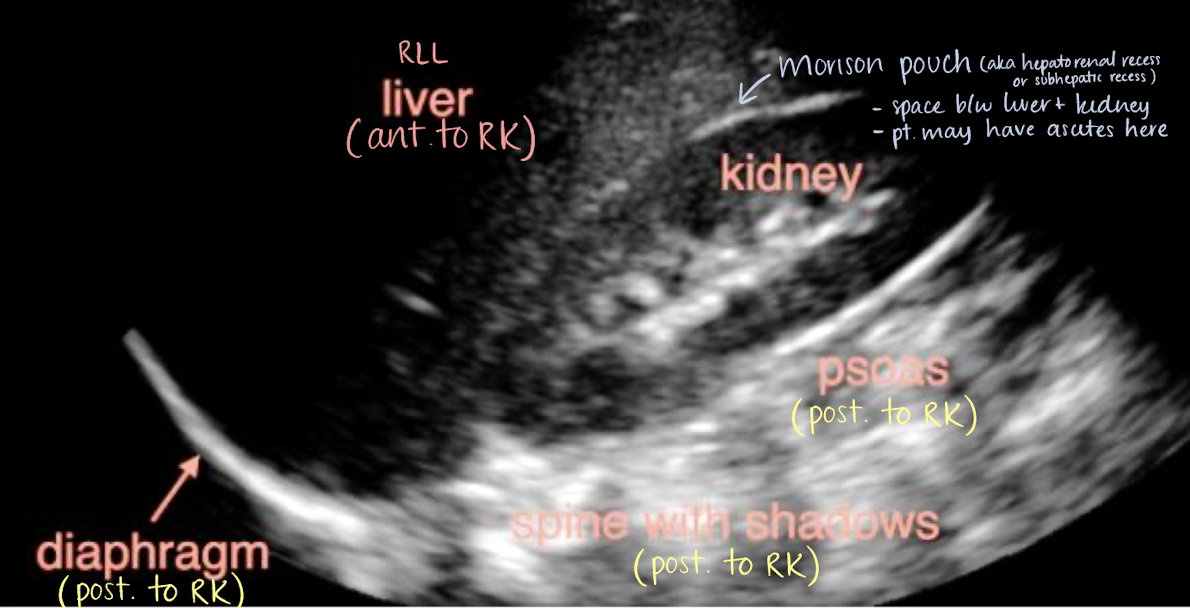

structures anterior to the RK and LK

anterior to RK

right adrenal gland

RLL

Morison’s pouch

2nd part of duodenum

hepatic flexure of colon

aka hepatorenal recess or subhepatic recess

space between liver and RK

patients may have ascites here

right posterior subhepatic space located anterior to kidneys and inferior to liver where fluid may collect